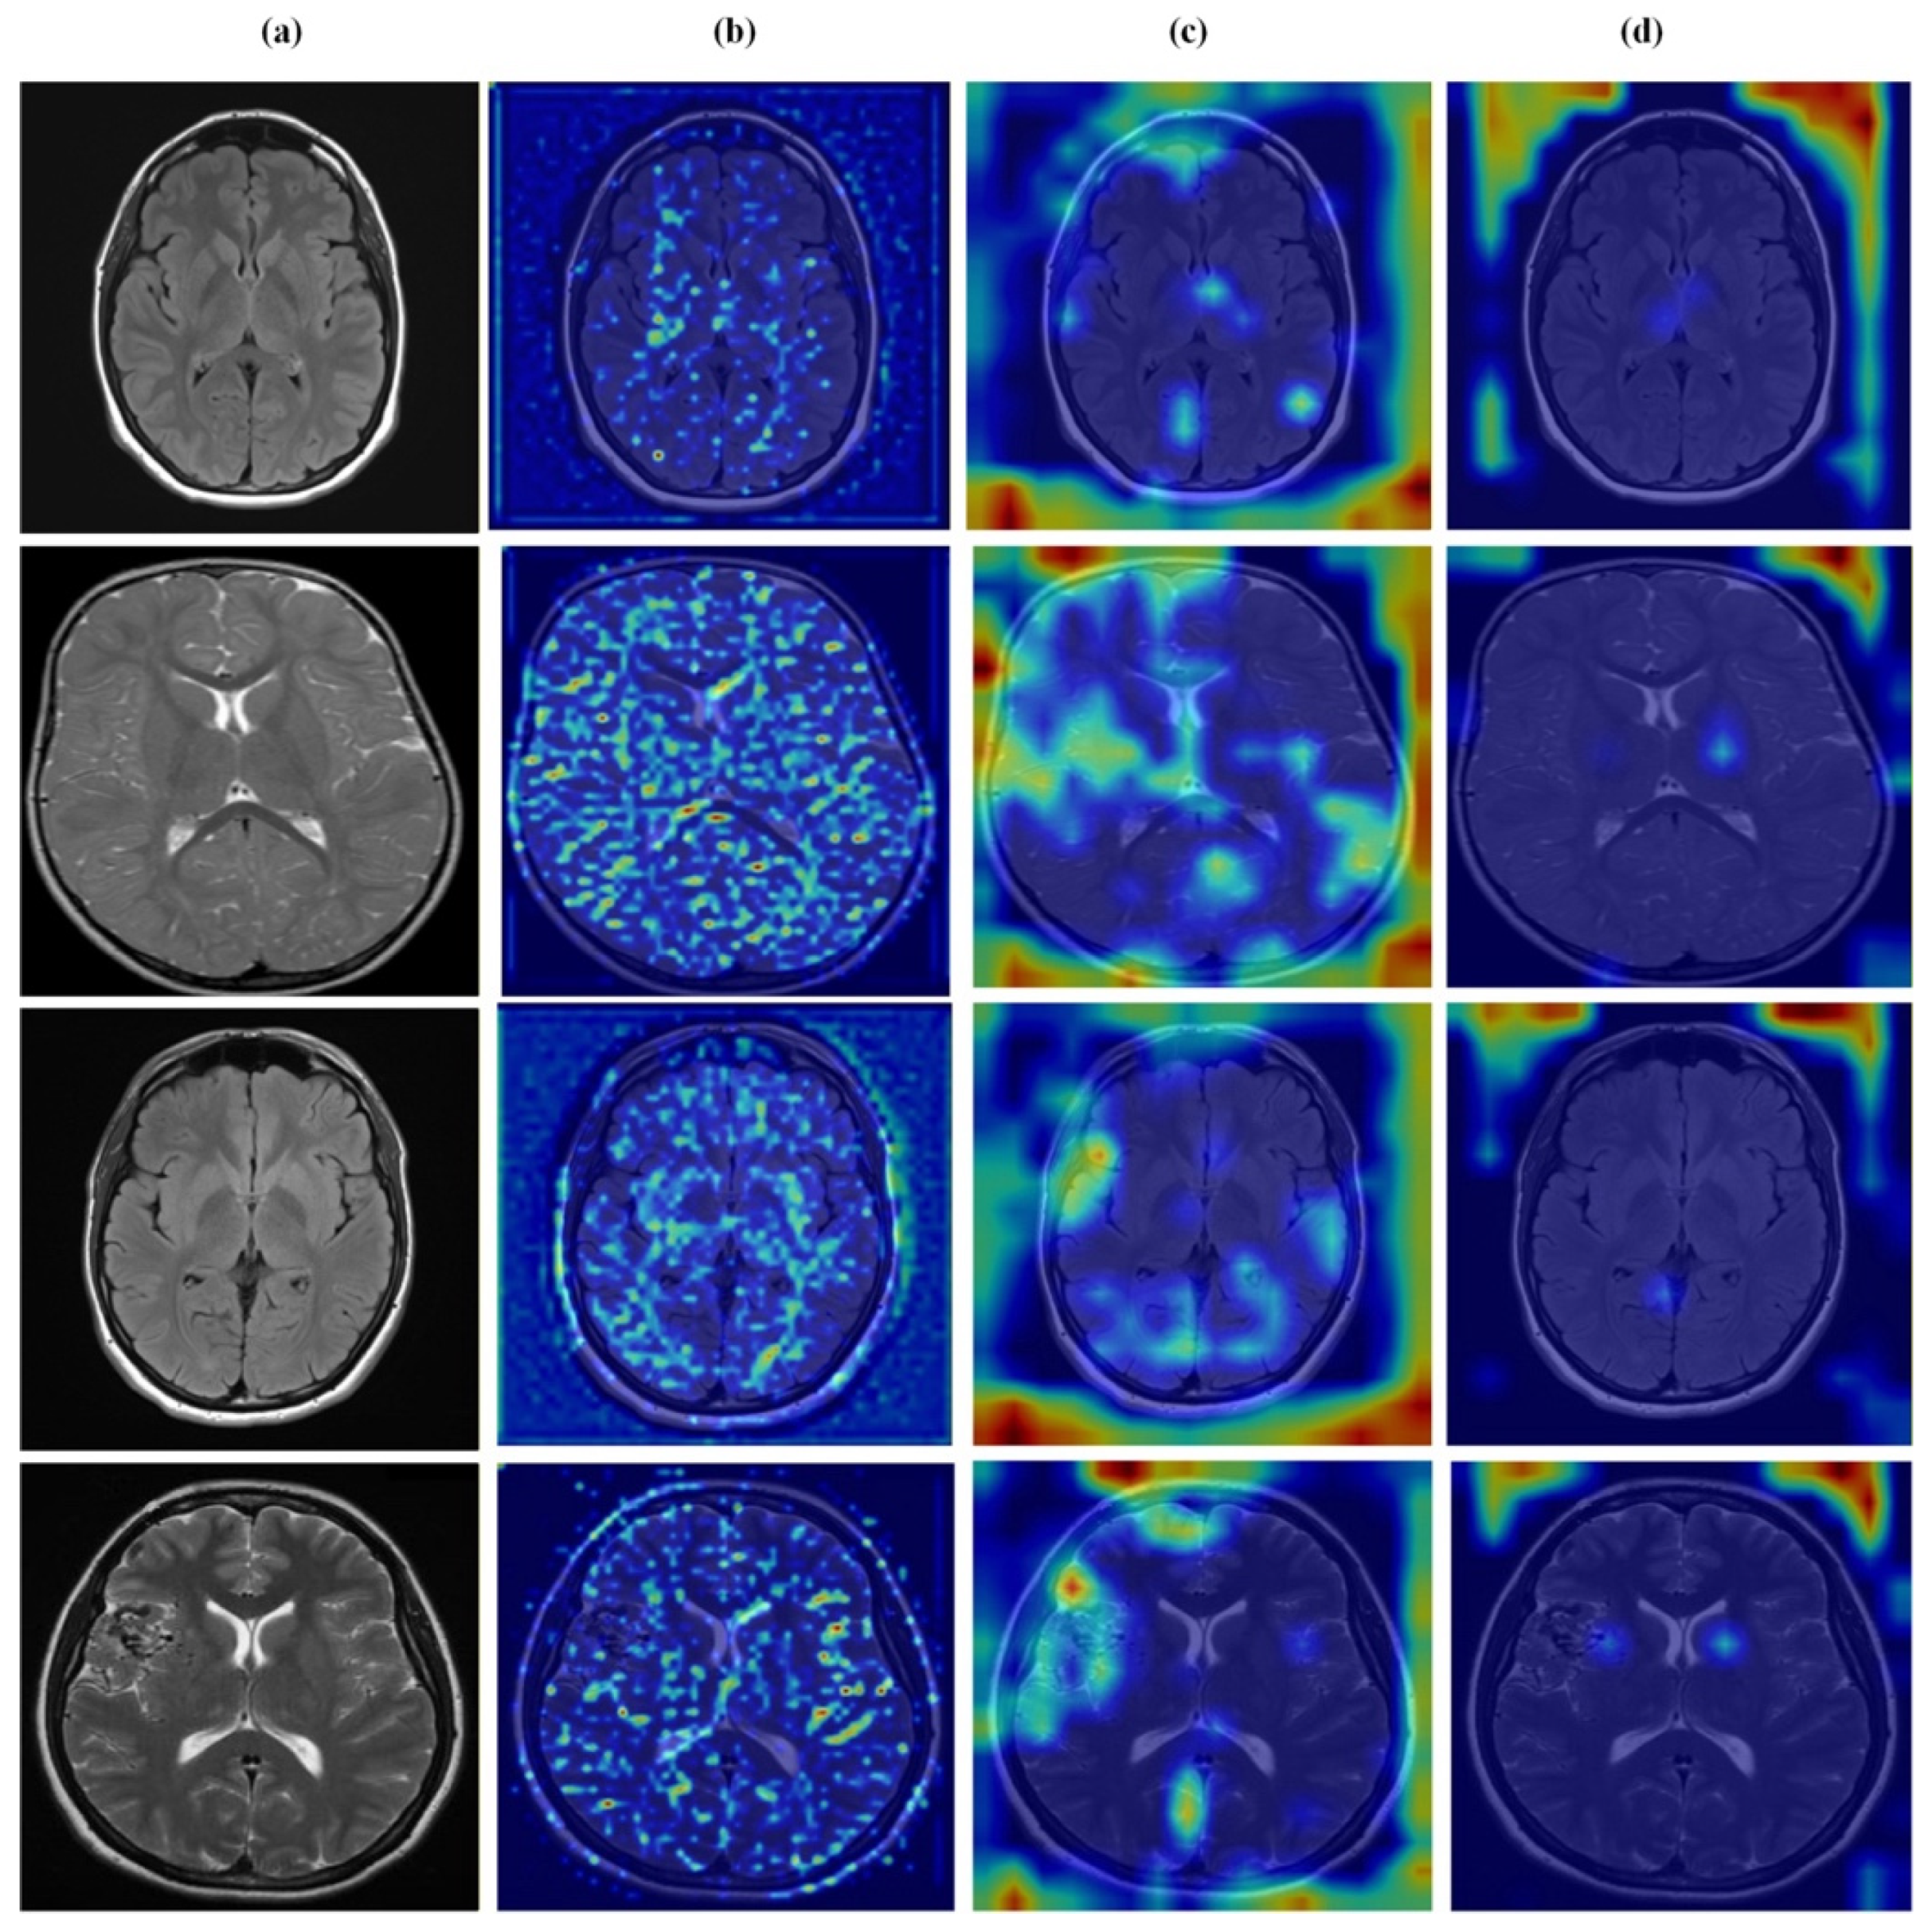

4.7. Feature Learning Analysis

Figure 12, Figure 13, Figure 14 and Figure 15 present Grad-CAM visualizations that trace the hierarchical feature learning of the proposed model across the four classes. Columns are organized as (a) input, (b) high-level features, (c) mid-level features, and (d) low-level features. In (d), the network emphasizes primitive cue edges, intensity transitions, and fine textures capturing sulcal boundaries, skull edges, and generic tissue patterns. Progressing to (c), activations become more structured and context-aware, highlighting coherent anatomical regions and diffuse hyperintense areas that provide spatial context for lesion localization. At (b), class-discriminative focus emerges with responses that contract tumor-centric hotspots for glioma and meningioma and to the sellar region for pituitary cases, while no_tumor images exhibit suppressed high-level responses, reflecting the model’s rejection of false lesion cues. This bottom-to-top progression from generic edges to task-specific evidence explains the model’s improved decision reliability and aligns with the multi-task design that encourages precise, clinically meaningful attention.

Figure 12.

Visual representation of feature activations in no tumor cases. (a) input, (b) low-level features, (c) mid-level features, and (d) high-level features.

Figure 13.

Visual representation of feature activations in glioma tumor cases. (a) input, (b) low-level features, (c) mid-level features, and (d) high-level features.